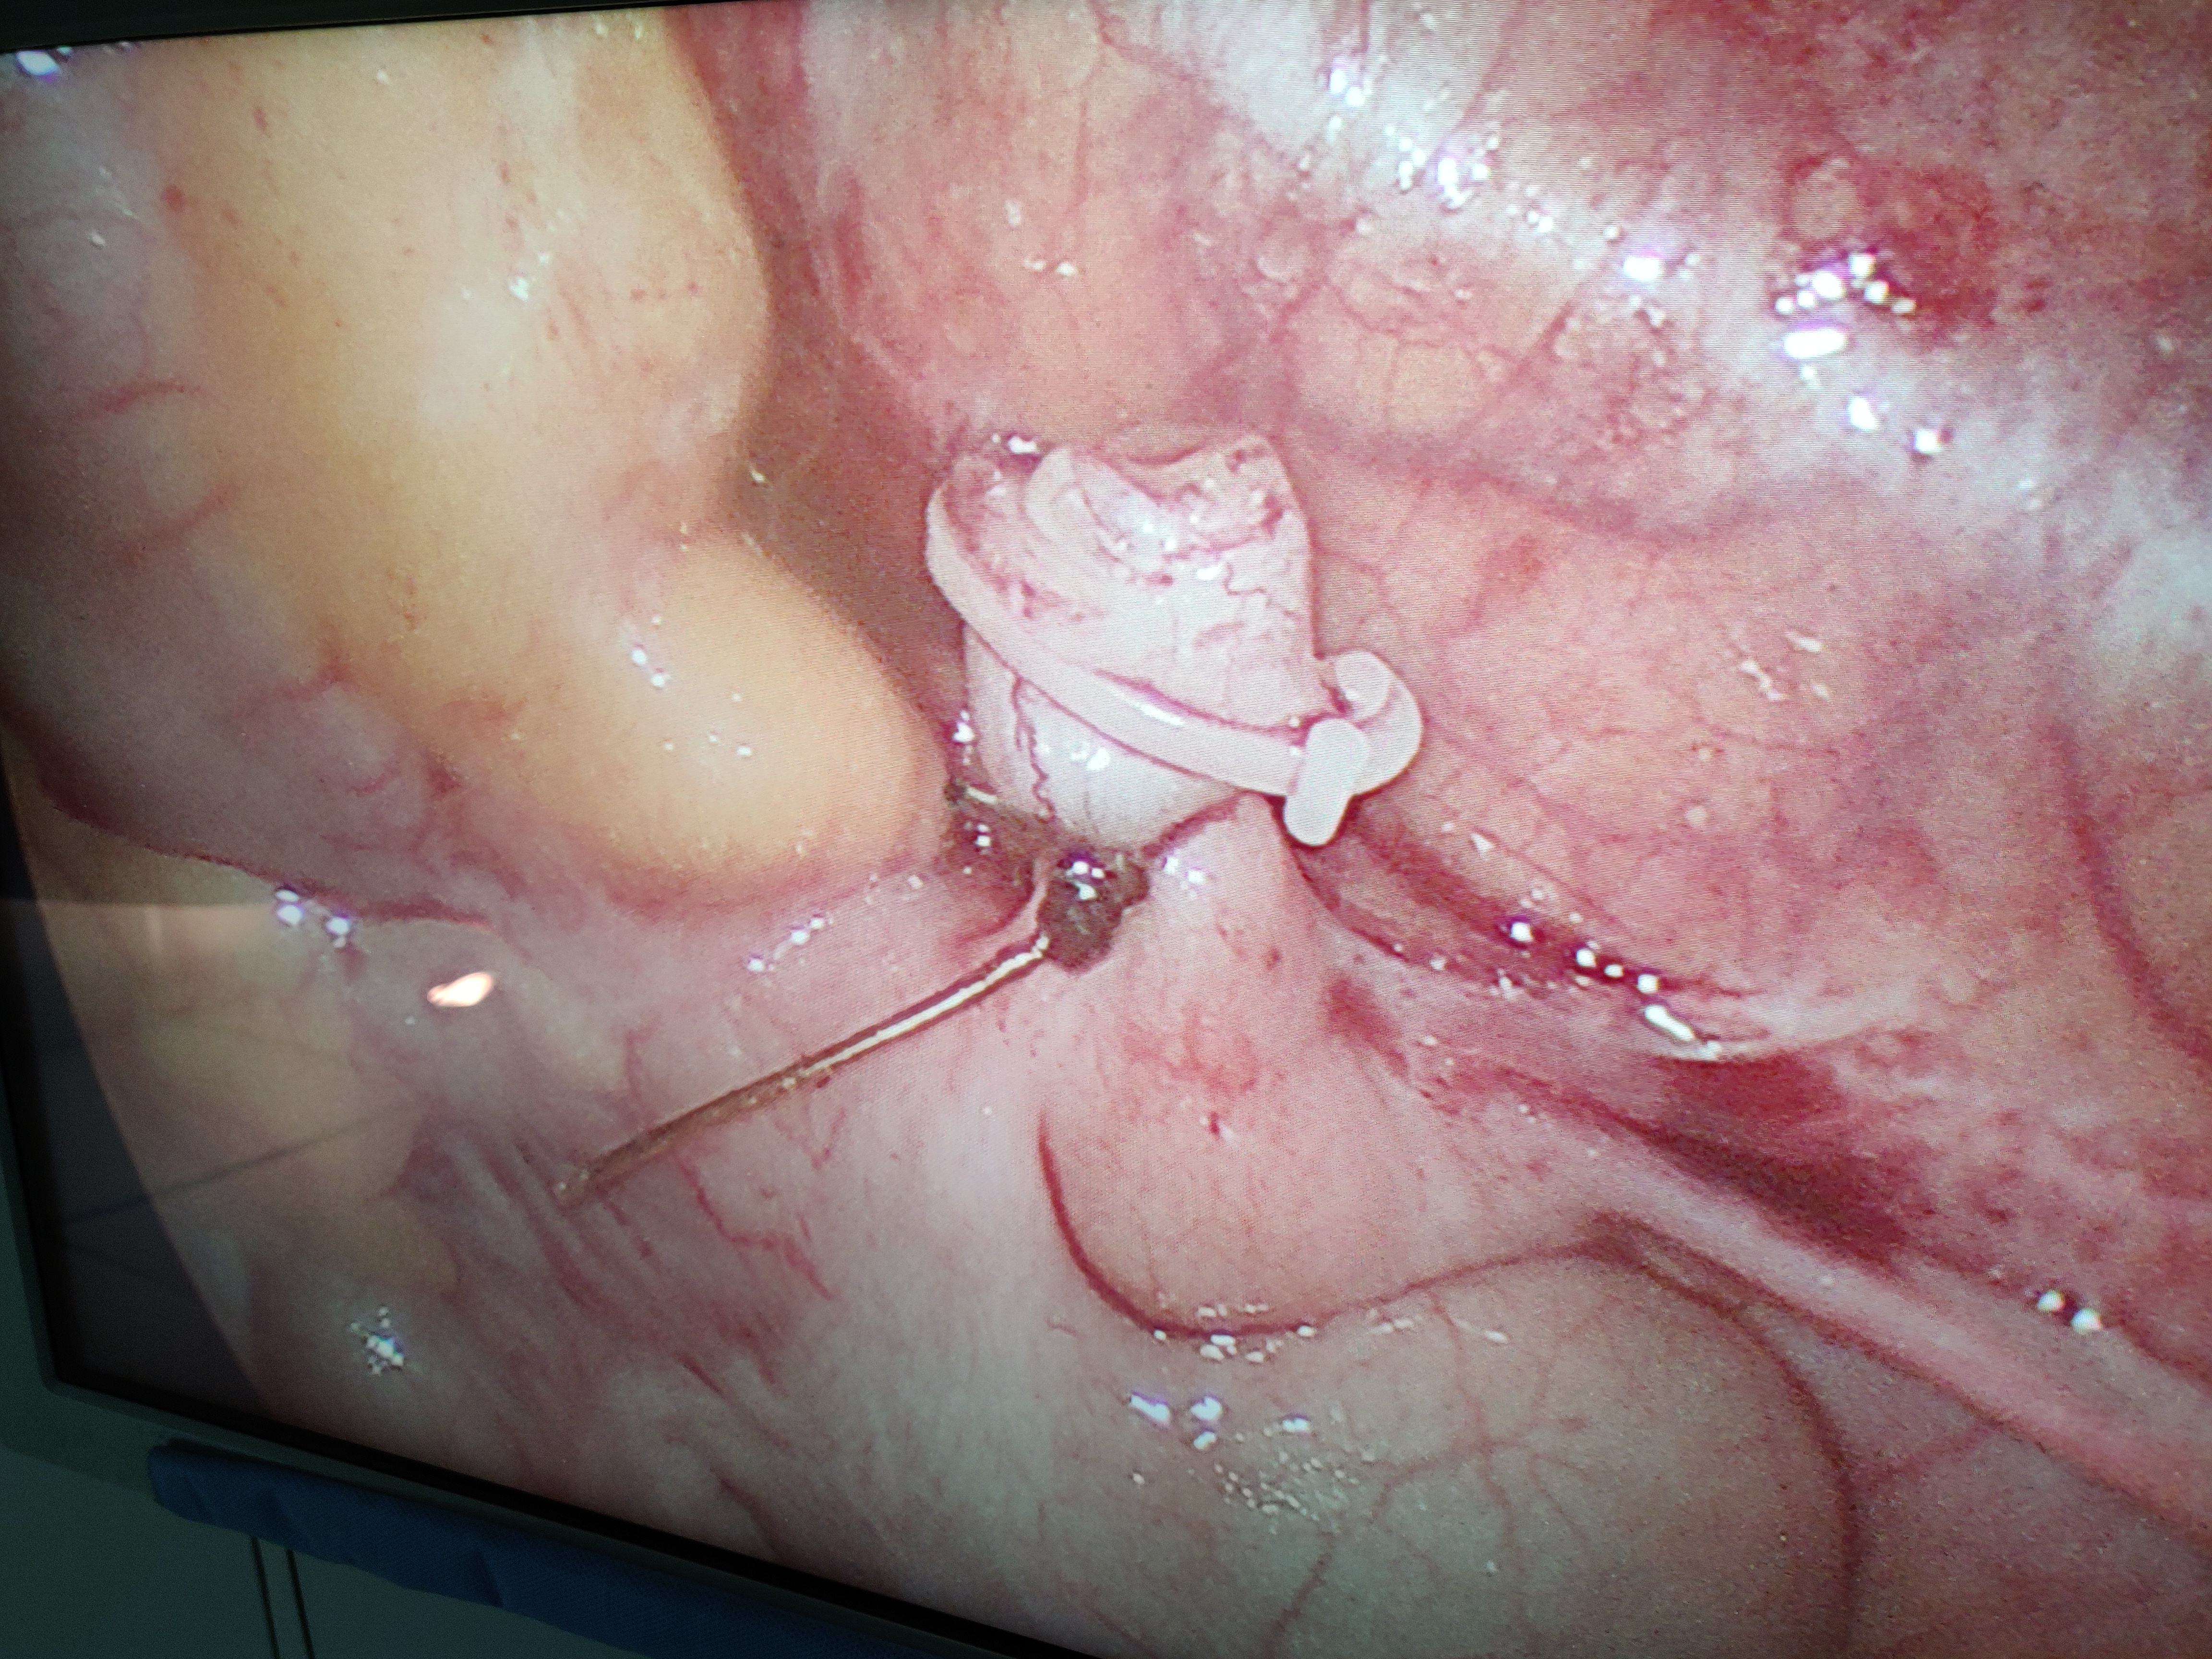

Dr. Pratik Biswas is a highly skilled and accomplished surgeon with an MBBS degree, DNB in General Surgery, and specialized training in Minimal Access Surgery (FMAS). His dedication to excellence is evident through his academic achievements and successful completion of programs from prestigious institutions like Holy Family Hospital and Zen Multi-Specialty Hospital. Dr. Biswas's commitment to staying updated in his field is further showcased by his completion of the FIAGES program. With a passion for surgery and a commitment to patient care, he is a trusted medical professional in the field.

Dedicated General Surgeon with special interest in Minimally Access Surgery. Efficient skills as an operative and assistant surgeon.

Minimally Invasive Surgery (MIS) is also used